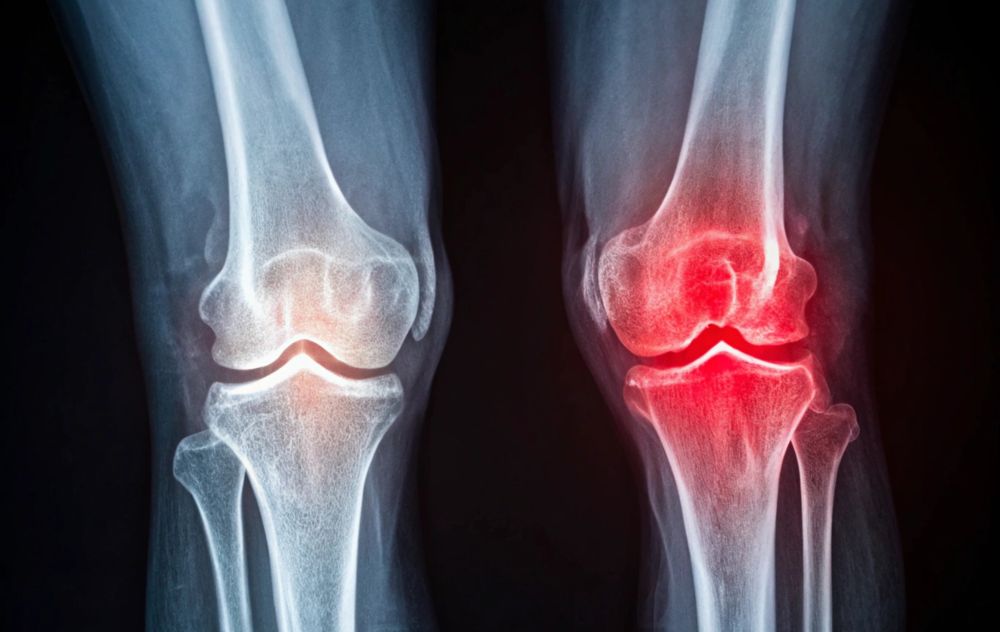

Non-Surgical Knee Pain Relief with Genicular Artery Embolization

At USA Pain Center, we specialize in treating knee pain caused by osteoarthritis, offering GAE (Genicular Artery Embolization) to help reduce knee pain and improve mobility. Whether you’re looking to avoid surgery or seeking relief from ongoing knee pain, USA Pain Center is here to help you get back to the activities you love.